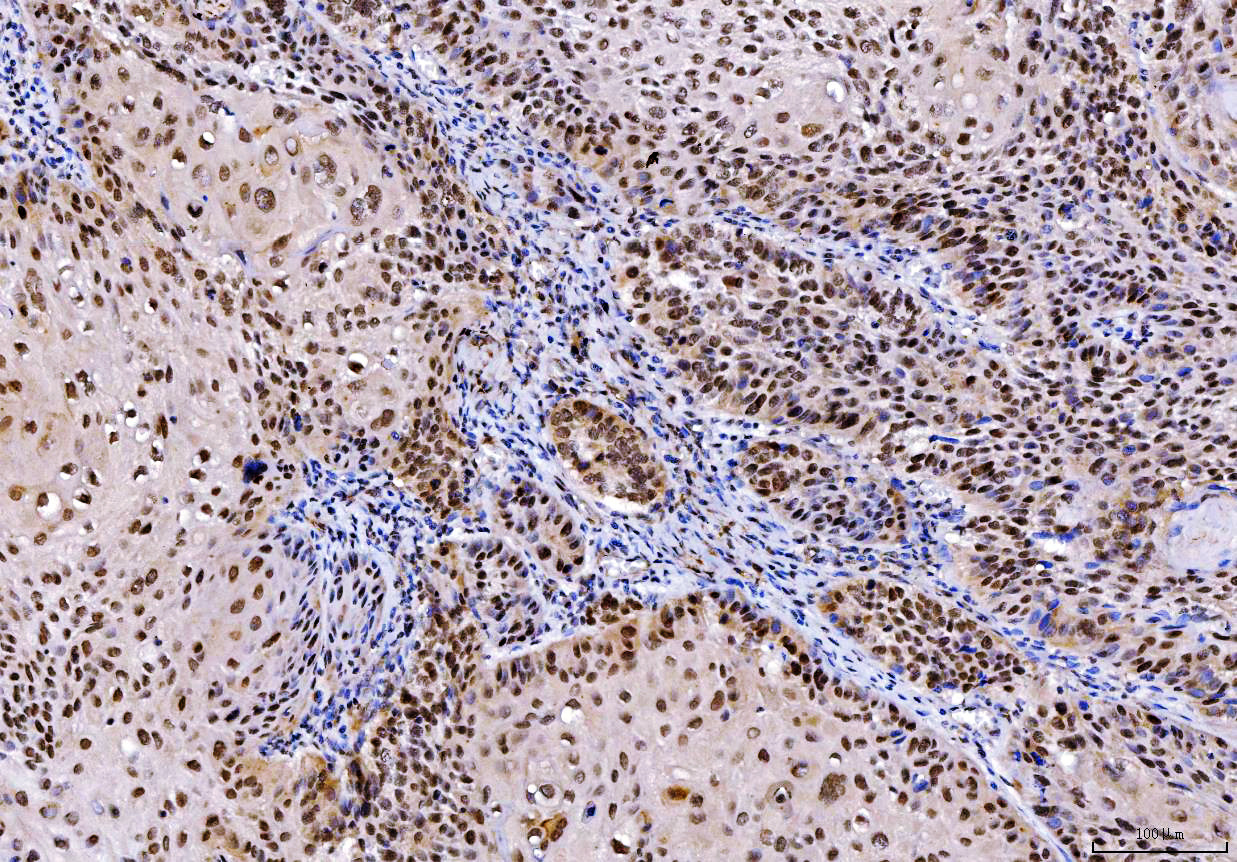

IHC analysis of PTPN6 using anti-PTPN6 antibody (M00938-2).

PTPN6 was detected in a paraffin-embedded section of human Laryngeal squamous cell carcinomas tissue. Biotinylated goat anti-mouse IgG was used as secondary antibody. The tissue section was incubated with mouse anti-PTPN6 Antibody (M00938-2) at a dilution of 1:200 and developed using Strepavidin-Biotin-Complex (SABC) (Catalog # SA1021) with DAB (Catalog # AR1027) as the chromogen.